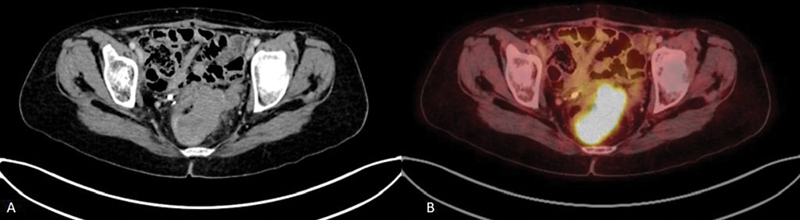

| Figure 4:(A, B) CECT and FDG PET-CT showing recurrence along the wall of the rectum in a patient with carcinoma ovary post neoadjuvant chemotherapy, interval debulking followed by adjuvant chemotherapy with elevated CA-125 levels on follow up.